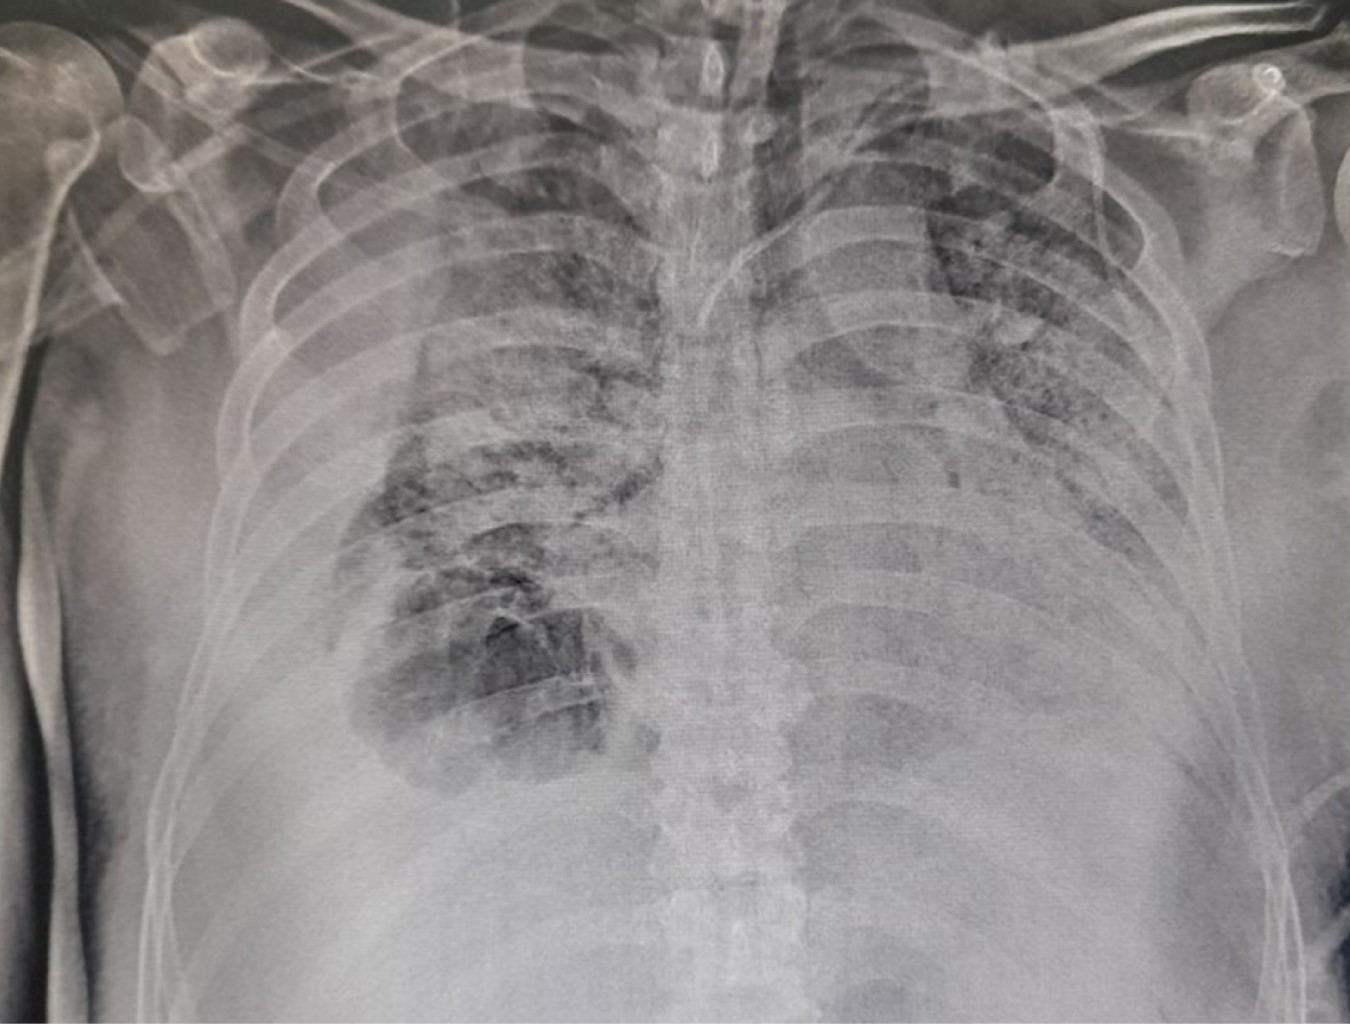

Se trata de un hombre de 56 años sin antecedentes de importancia, el cual presenta cuadro de fiebre, tos, rinorrea, malestar general. El día dos de iniciado el cuadro clínico se realiza reacción en cadena de la polimerasa (PCR) para el SARS-CoV-2 cuyo resultado fue positivo, recibe tratamiento domiciliario. El día tres de iniciado el cuadro es trasladado a un hospital privado por persistir con disnea y desaturación requiriendo administración de oxígeno suplementario. El día 10 de iniciado el cuadro muestra datos de dificultad respiratoria e hipoxemia ameritando intubación orotraqueal e inicio de ventilación mecánica por presentar síndrome de insuficiencia respiratorio agudo (SIRA) severo de acuerdo a la clasificación de Berlín (PaO2/FiO2 70 mmHg). Durante su estancia recibe tratamiento a base de levofloxacino, tocilizumab y dexametasona, por la mala evolución clínica requiere de parámetros altos de ventilación y apoyo con vasopresor. Se decide traslado a nuestro hospital 28 días después de haber iniciado el cuadro clínico. Es ingresado a terapia intensiva donde se le realizó traqueostomía percutánea por ventilación prolongada, permanece con requerimientos altos de fracción inspirada de oxígeno. El día 40 de iniciado el cuadro se documenta en radiografía de tórax imagen radiolúcida en tercio inferior derecho compatible con bulla pulmonar (Figura 1). Se realiza tomografía computarizada de tórax, la cual reporta área de atrapamiento aéreo con presencia de septos en su interior en segmento 10 del pulmón derecho (S10) compatible con bulla y neumotórax (Figura 2).

Figura 1